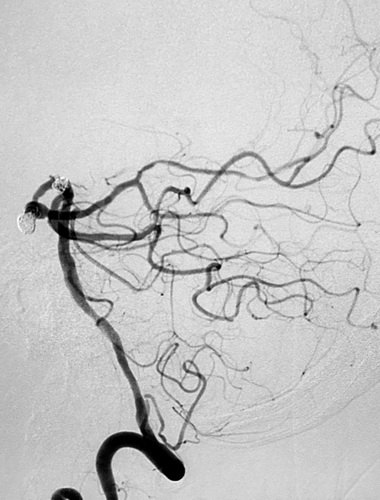

全脑血管造影提示:左侧颈内动脉主干血管明显狭窄,大脑中动脉及前动脉基本闭塞,左侧供血差,颈外动脉有少量代偿,左侧椎动脉造影示右侧大脑后动脉P2段夹层、基底动脉顶端,分别大小为6 mmX5mmX4mm瘤颈约5mm;4 mmX4mmX3mm瘤颈约3mm。

先微导管Echelon到位右侧大脑后动脉瘤,小心成篮,在保留大脑动脉通畅情况下尽可能地多栓塞动脉瘤体部与顶部,对瘤颈的栓塞不强求;分别为Presidio 3D 5mmX17cm,EV3 3D 3mmX6cm,3mmX4cm,2mmX4cm,在观察形态学弹簧圈对载瘤动脉无明显影响后实行解脱,最后造影见右侧大脑后动脉动脉瘤顶端不显影,近端于瘤颈处仍有部分显影。 之后再退至基底动脉瘤内,行部分栓塞,EV3 3D 4mmX8cm,2mmX4cm, 1.5mmX2cm,1.5mmX2cm,不用支架,是因为考虑病情较重,脑室较大,术后可能要行脑室外引流术,而支架应用则需用双抗会造成手术操作困难。后期拟再行补救支架手术。

ICA造影

首先栓晒右侧大脑后动脉瘤

右侧大脑后动脉瘤术后侧像